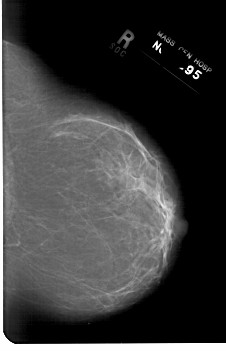

A_1169_1.RIGHT_MLO

RIGHT_CC LINES 6661 PIXELS_PER_LINE 4291 BITS_PER_PIXEL 12 RESOLUTION 43.5 NON_OVERLAY